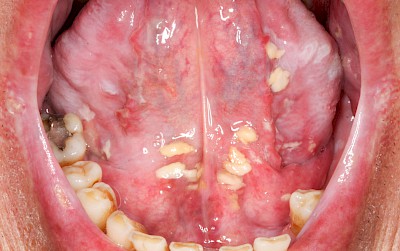

Pilzerkrankung

Pilze gehören zur physiologischen Mundflora und sind grundsätzlich nicht problematisch. Schlechte Mund- bzw. Prothesenhygiene und ggf. gleichzeitig übermäßiger Verzehr kohlenhydratreicher Nahrung kann das Pilzwachstum jedoch begünstigen Der typische Pilz im Mund ist Candida albicans, ein sprossbildender Hefepilz. Bei übermäßigem Pilzwachstum spricht man von einer Pilzerkrankung, Pilzfinfektion, Pilzbefall, Soor oder Candidose. Pilzerkrankungen können auch im Fall guter Mundhygiene auftreten bei:

- Dauerhaftem Gebrauch von Asthma-Spray (Kortison)

- Geschwächtem Immunsystem (nach Transplantation, bei Chemotherapie, bei Bestrahlung Kopf-Hals-Bereich)

Wenn die Intensivierung der Mundpflege allein den Pilzbefall nicht zu verhindern vermag, sind in manchen Fällen dann zusätzliche Maßnahmen wie Medikamente gegen Pilze (Antimykotika) nach ärztlicher Rücksprache angezeigt.

Beispiele25 Bilder